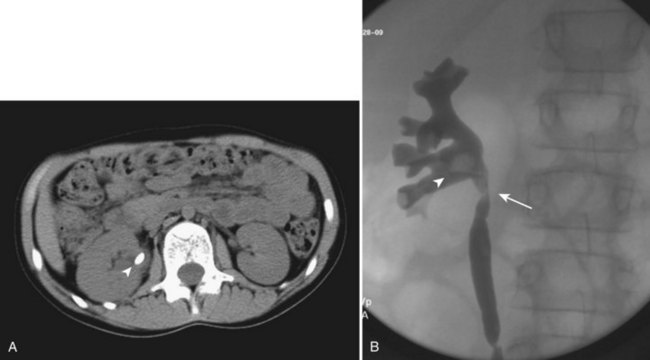

Figure 135–1 CT scan (A) and retrograde pyelogram (B) in a 10-year-old female with glucose transport deficiency demonstrating a 9-mm renal pelvic stone (arrowheads). Nephrolithiasis was secondary to profound hypocitruria and hypercalciuria. Primary ureteroscopy could not be accomplished because of a narrowed segment of proximal ureter (arrow). Following 8 weeks of ureteral accommodation with an indwelling stent, flexible ureteroscopy with laser lithotripsy and stone basketing was performed.